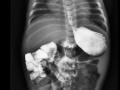

Má-rotação Intestinal

Pediatria

Abdome

Trato gastrointestin...